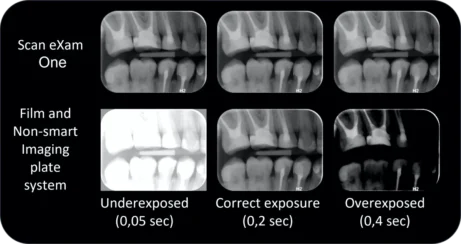

Automatizované snímky

Automatické kompenzace přeexponování i podexponování. Jasné a ostré intraorální snímky přesně reprodukují úrovně šedi, aby zobrazily veškeré potřebné diagnostické detaily.